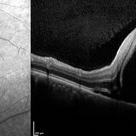

Preeclampsia in a 30-Year-Old - OCT- LE

Nov 25 2015 by Roy Schwartz, MD

A 30-year-old presented with central scotoma and blurred vision a day following C section for preeclampsia

Photographer: Galit Yair Pur

Condition/keywords: blurred vision, central scotoma, preeclampsia